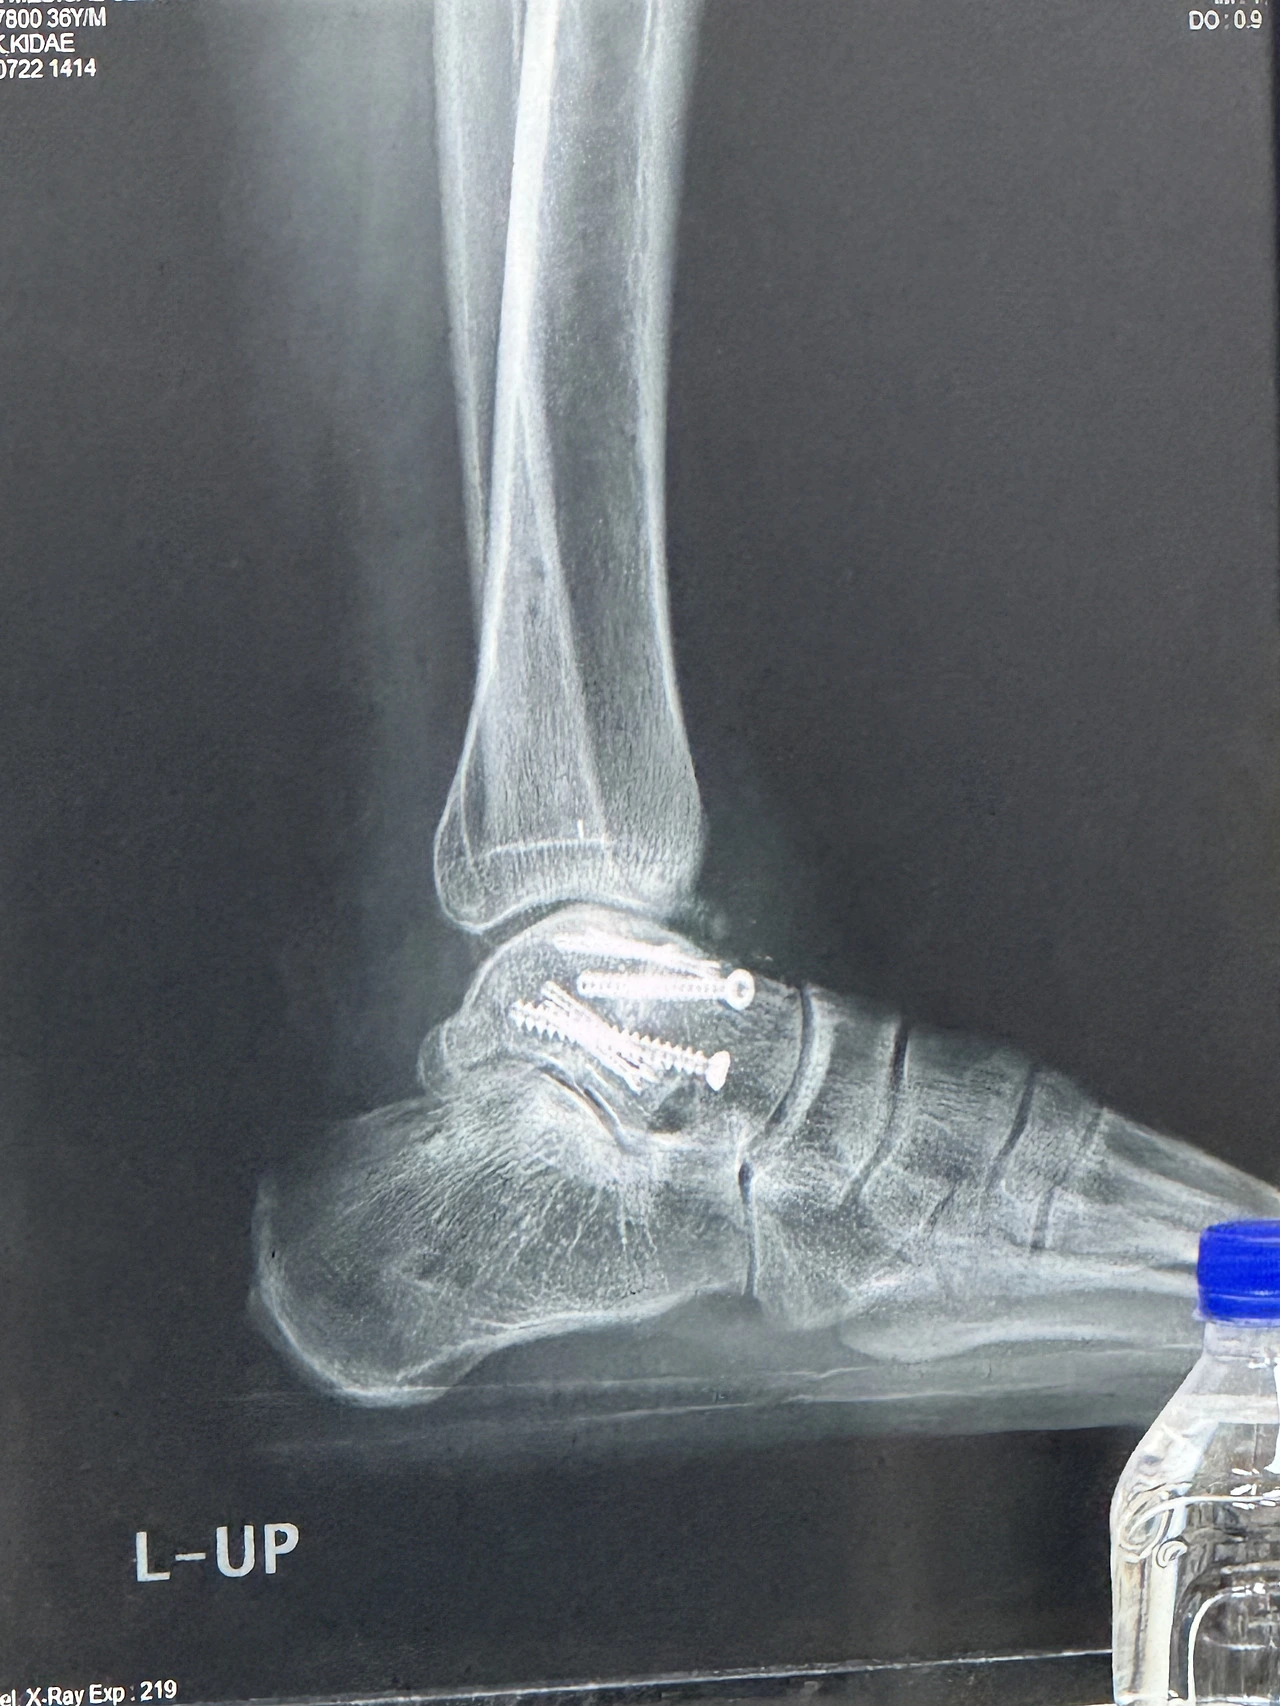

의사 선생님은 외고정기 제거 수술은 이전 수술보다 간단한 수술이라고 했다. 이전의 뼈에 나사를 박고 인공뼈와 나의 골반에서 추출한 뼈를 이식해서 원래뼈의 모양을 구현하는 수술은 6시간 정도 걸렸다. 반면 이번 수술은 1시간 내외로 수술시간도 짧았다.

수술 전날 병원에 입원하여 여러 가지 검사를 했다. 병원에 있는 동안 수없이 바늘에 찔렸지만 검사하는 동안 찔린 바늘은 아직도 적응할 수 없었다. 다음날 수술실에 들어가기 전 긴장되는 것은 첫 수술 할 때와 마찬가지였다. 간단한 수술이라고 했지만 척추마취와 수면 마취를 해야 했다. 수술 후 철제 보형물이 박혀있던 자리의 살들이 아물 때까지 씻지는 못했다.

수술 후에도 아버지는 일주일에 1번 병원에 데려다주셨다. 발목을 거이 움직일 수 없었다. 물리치료사가 내 발을 보고 시체 같다고 했다. 나는 그 말을 듣고 마사지나 더 시원하게 해줬으면 하고 속으로 생각했다. 종아리 근육이 많이 수축된걸 육안으로 확인할 수 있다. 누워있는 동안 허벅지는 다른 부위보다 운동도 많이 했고, 육안으로도 다른 쪽과 비교하여 크게 차이가 안나 걱정을 많이 안 했었다. 물리치료사님의 말로는 허벅지는 지방이 많아서 별로 티가 안 나지만 근 육은 많이 빠졌을 거라고 하셨다. 수술한 쪽의 허벅지에 힘을 주어도 근육이 만저지지 않았다. 앞으로 발목에 박혀있는 핀을 빼는 수술을 하기 전까지 운동을 열심히 해서 근육량을 많이 늘려놔야겠다고 다짐했다.